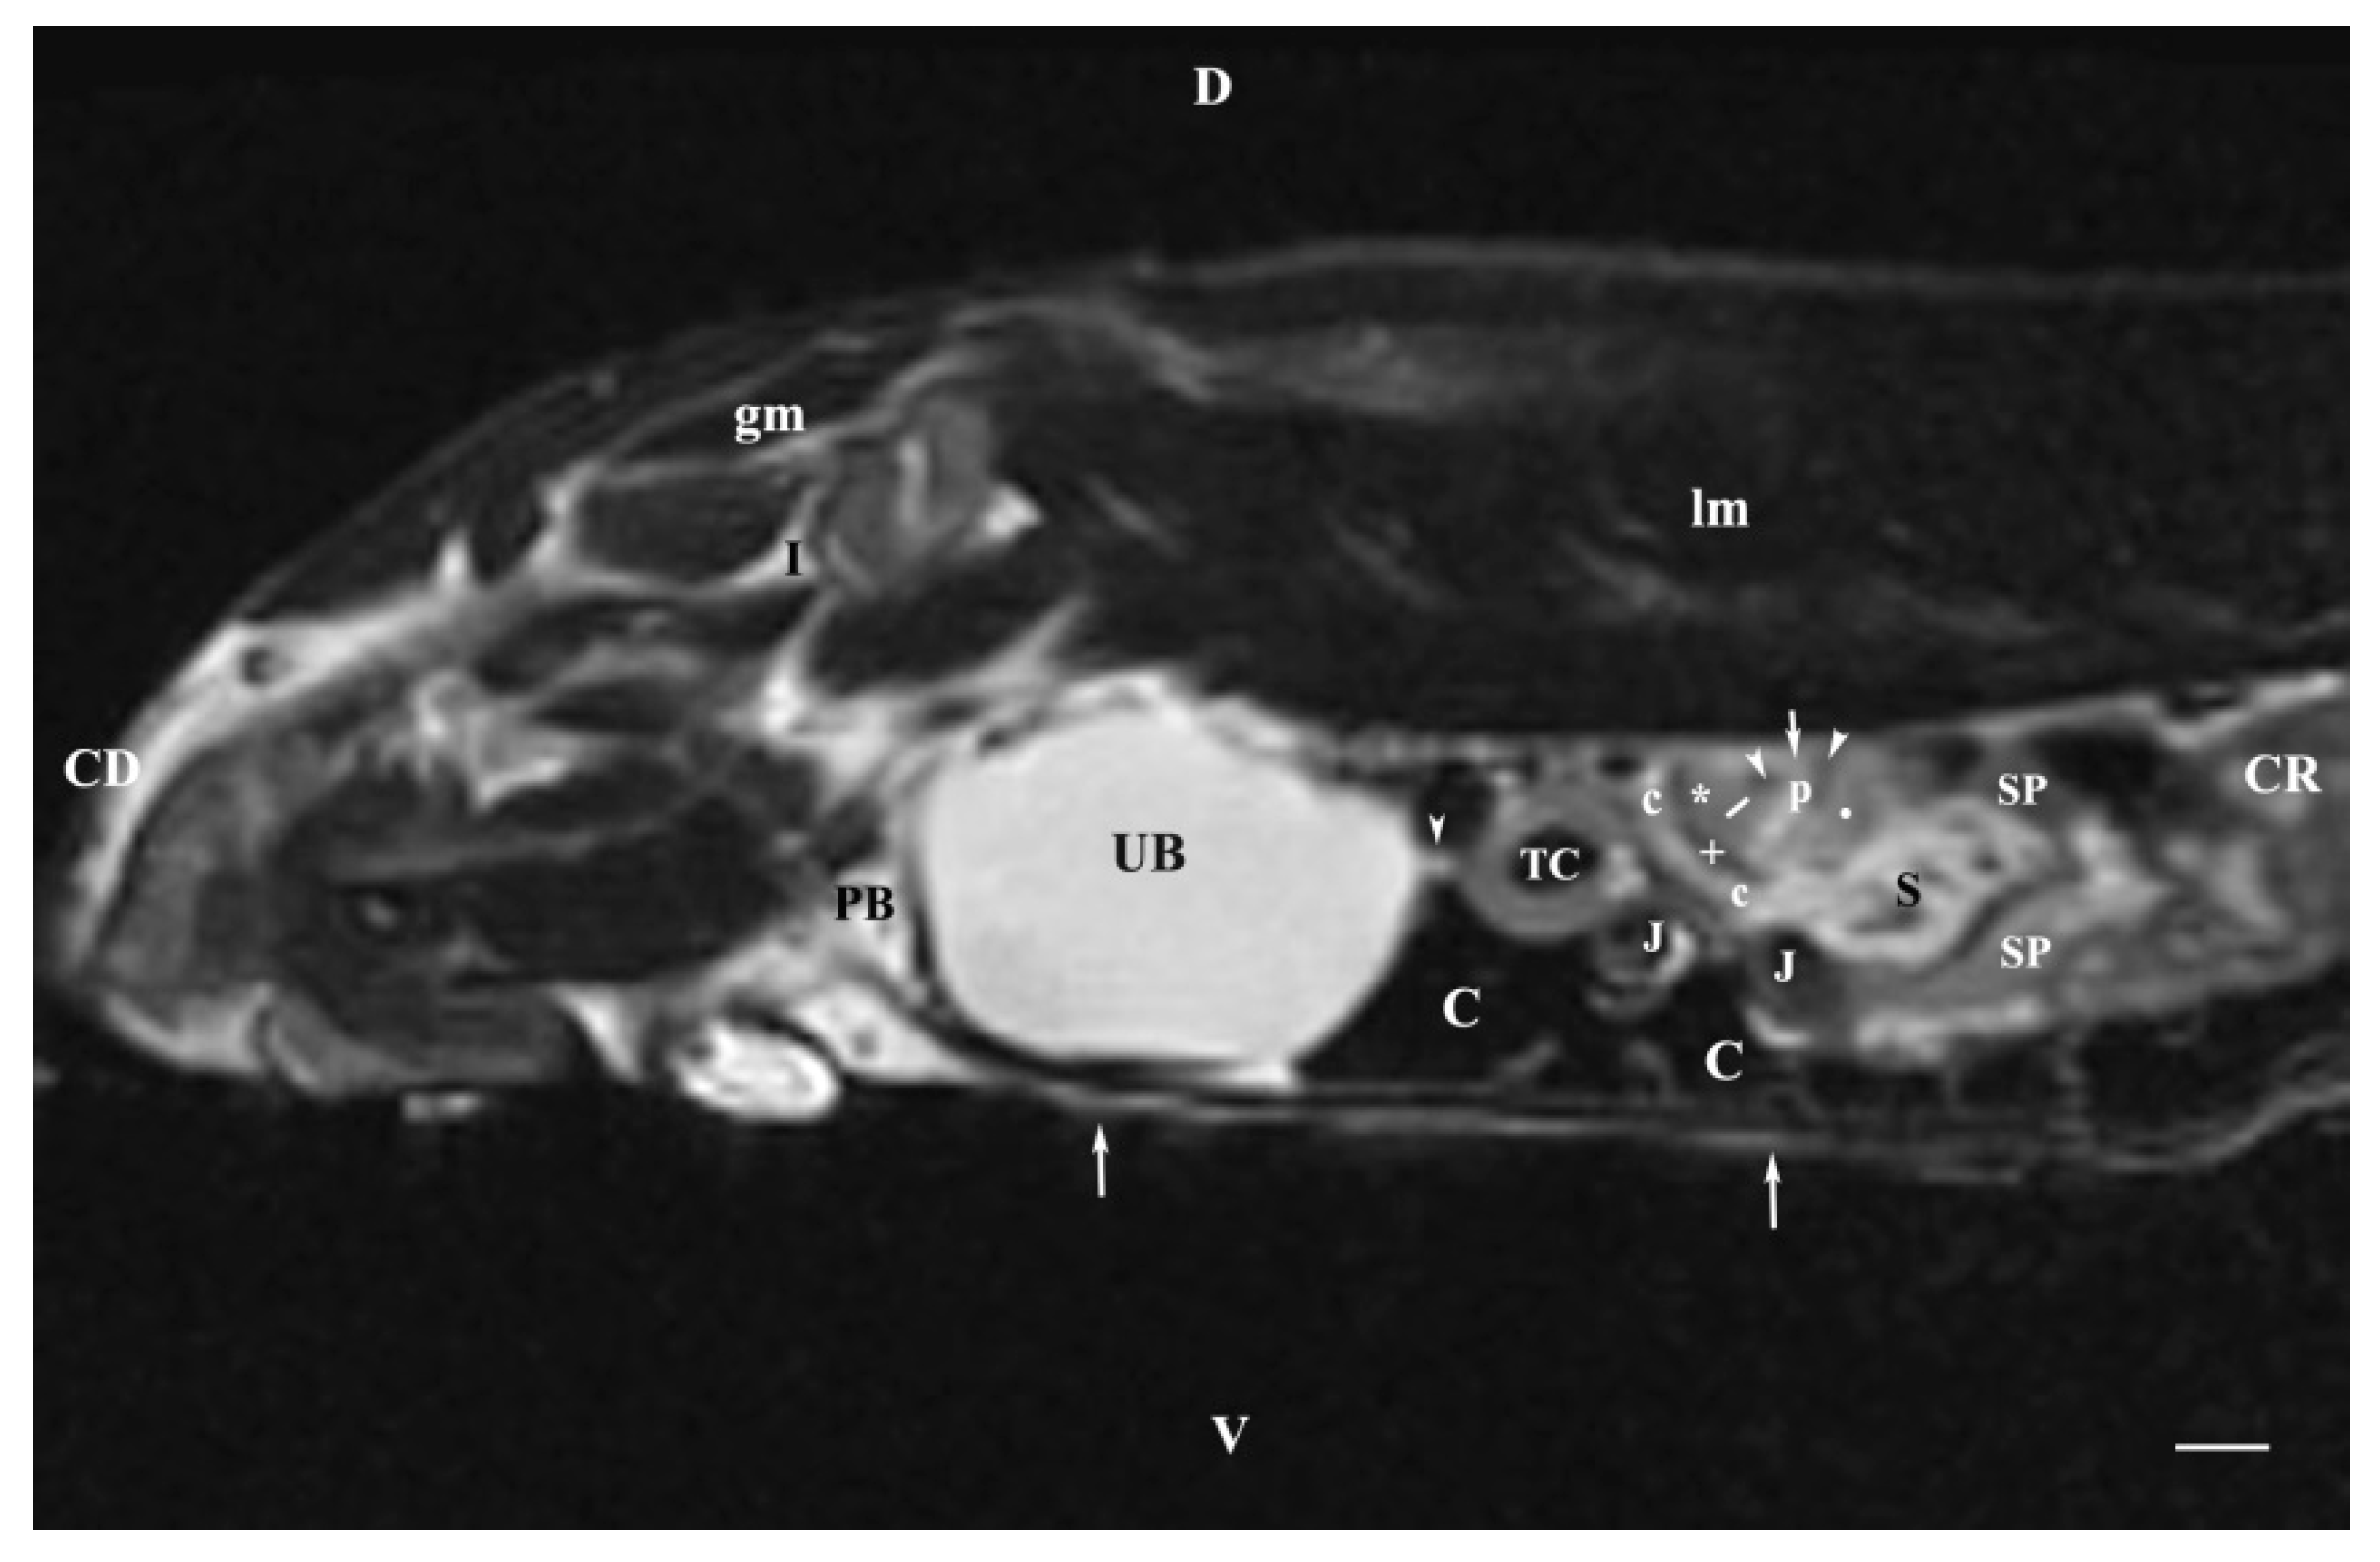

3.2. Sagittal MRI